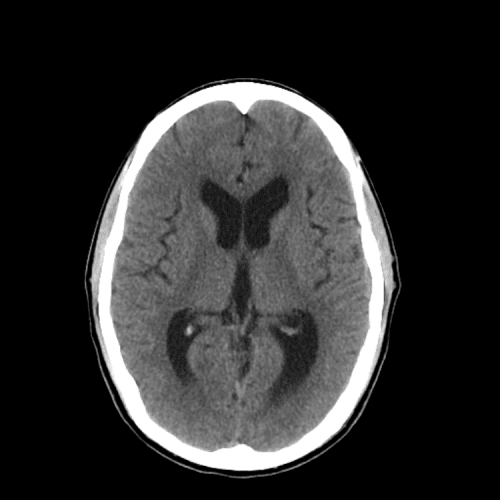

PCA infarct